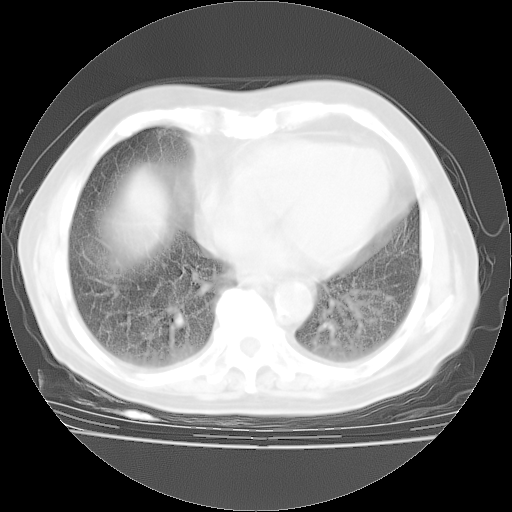

4月28日肺部CT——再次出现类似去年5月9日——磨玻璃样、间有“粟粒样”改变。

个人阅读4.14日肺部CT平扫:纵隔窗无异常,但肺窗示:双下肺内、后基底段有片絮状侵润影,部位以后基底段为著,以间质改变为主,呈急性肺泡炎征像,和首次住院影像学有相似之处。仅是个人读片,明日请相关专家再读片哈。其它建议同上。

1、108#的是4月14日的胸部CT(发此贴时还没看着28日的CT)。14日的胸部CT其实已经出现改变(如108#所述),个人认为28日的胸部CT除纵膈窗疑似有双侧胸膜增厚或少量胸积液(可行胸部B超明确)外,与4月14日对照病变有所加重;2、已经给予“异烟肼、利福平、乙胺丁醇”抗痨治疗?如果是,甲强龙80mg可缓慢减量;如果环磷酰胺已停用,暂不使用;3、中性粒细胞92%,明显升高,目前体温情况?注意合并细菌感染可能,使用左氧氟沙星情况下,是否联用B-内酰胺类抗菌药物?另外是查免疫全套非风湿全套。